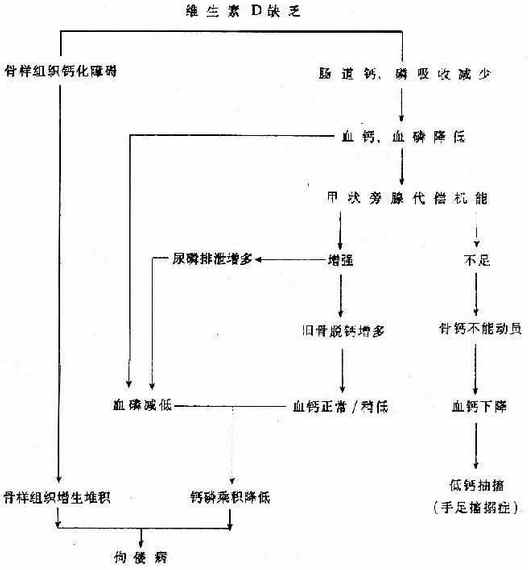

维生素D缺乏时,肠道钙、磷吸收减少,血中钙、磷下降。血钙降低剌激甲状旁腺激素(PTH)分泌增加,加速旧骨吸收,骨盐溶介,释放出钙、磷,使血钙得到补偿,维持在正常或接近正常水平;同时大量的磷经肾排出,使血磷降低,钙磷乘积下降,当钙磷沉积降至40以下时,骨盐不能有效地沉积,致使骨样组织增生,骨质脱钙,硷性磷酸酶分泌增多,临床上产生一系列骨骼症状和血生化改变。(见图3-1)。

图3-1 佝偻病及婴儿手足搐搦症发病机理图